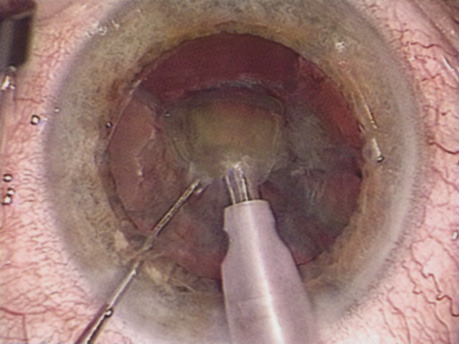

B-SCAN ULTRASOUND.

A mature cataract precludes visualization of the fundus. A B-scan ultrasonographic examination provides a real-time, two-dimensional (2D), cross-sectional image of the globe along the marked axis of the probe (Fig. 3). Cataracts are more common in patients with chronic retinal detachment, prior trauma, or intraocular tumors; therefore, a B-scan study is helpful in excluding structural posterior segment pathology before surgery on a mature cataract. Although a negative result to B-scan evaluation is reassuring, the surgeon should remember that it does not predict postoperative visual outcome. The B-scan can be thought of as a picture of Cincinnati from an airplane; the office buildings may all be standing, but you cannot tell whether the people in them are working.

Fig. 3. This B-scan ultrasound shows a normal looking posterior pole, without retinal detachment or intraocular mass. The vitreous cavity is echo lucent.